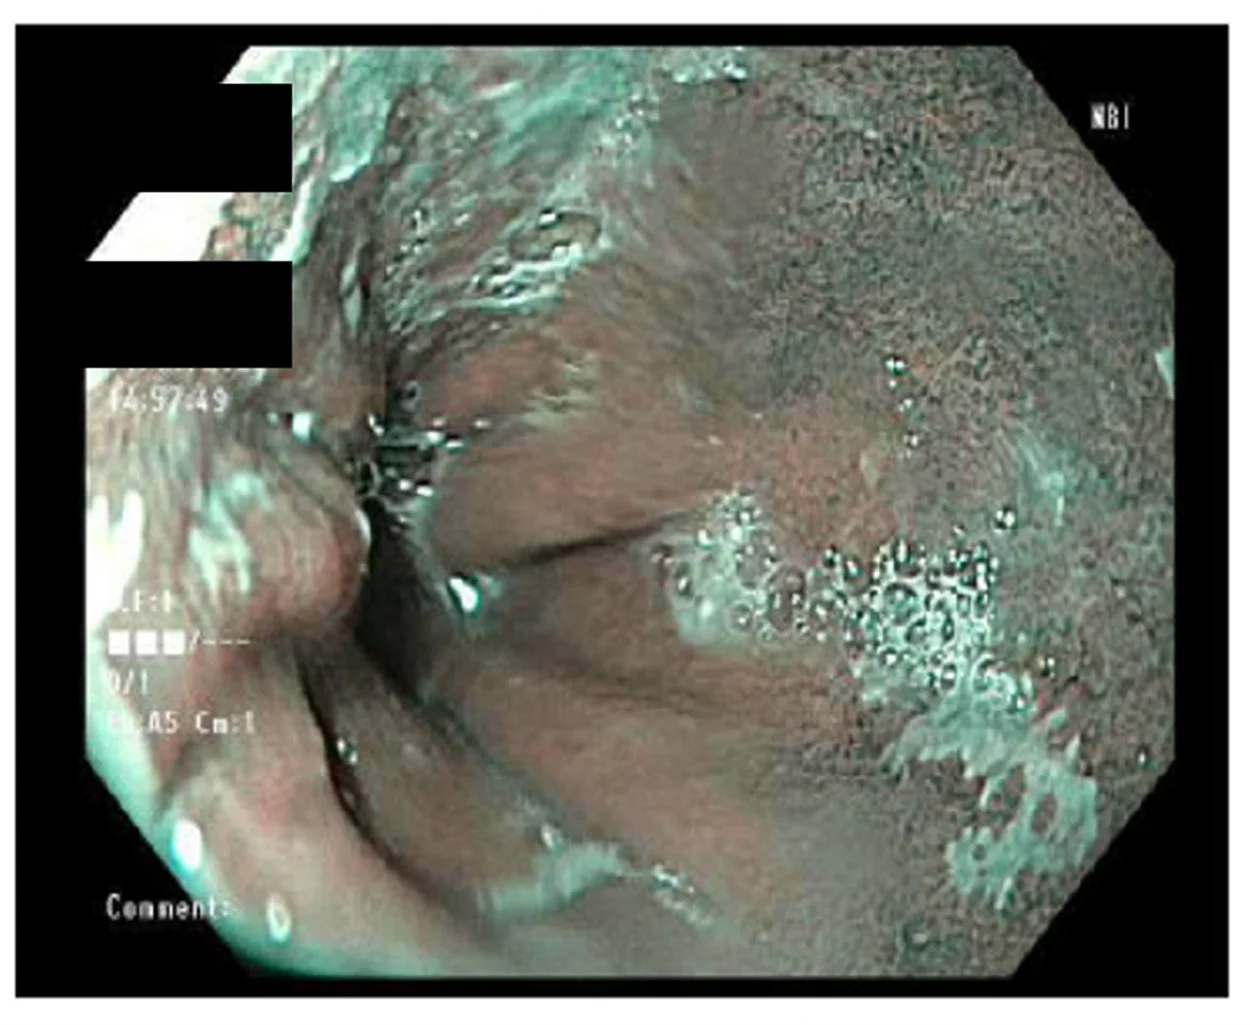

An 81-year old male patient found himself on the fence about whether to continue ongoing surveillance of his BE. Up to this point he had no family history of EAC or even a diagnosis of dysplasia that would give him an objective reason to seek more aggressive management of his BE.

- In surveillance for NDBE